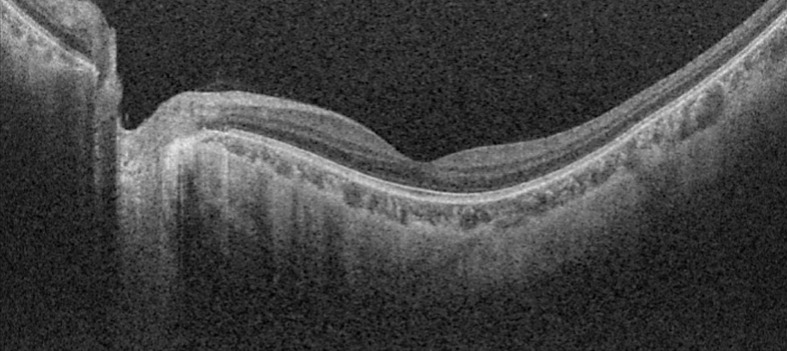

Case presentation: We report 2 cases of retinal detachment following roller coaster riding. The first, a 24-year-old woman with a family history of retinal detachment, presented with floaters after consecutive rides and was found to have an inferior temporal macula-sparing retinal detachment with associated retinal breaks. The second case, a 25-year-old female with a history of high myopia, presented with visual field defect and was found to have a macula-on retinal detachment with an accompanying tear at the edge of an area of lattice degeneration. Both were successfully treated with pneumatic retinopexy followed by laser retinopexy.